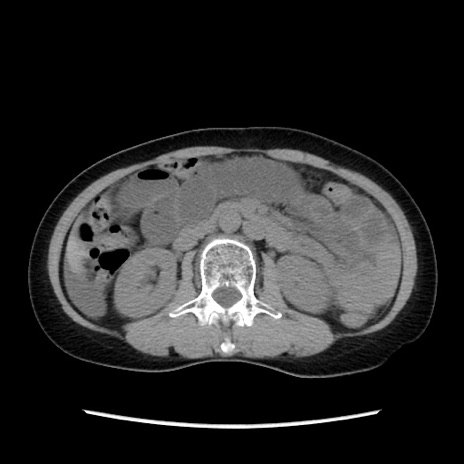

症例32(横断像)

【症例】40歳代 女性

【主訴】上腹部痛、嘔気・嘔吐

【現病歴】約9時間前頃から急に上腹部痛、嘔気、嘔吐が出現。改善しないため救急要請。

【既往歴】子宮頚癌(広汎子宮全摘術、放射線療法)、腸閉塞

【身体所見】腹部:平坦、軟、腸雑音亢進、上腹部を中心に腹部全体に圧痛あり。

【データ】WBC 8400、CRP 0.03